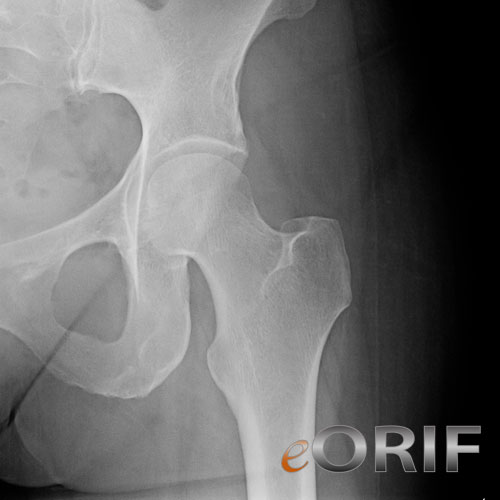

Normal Hip Xray